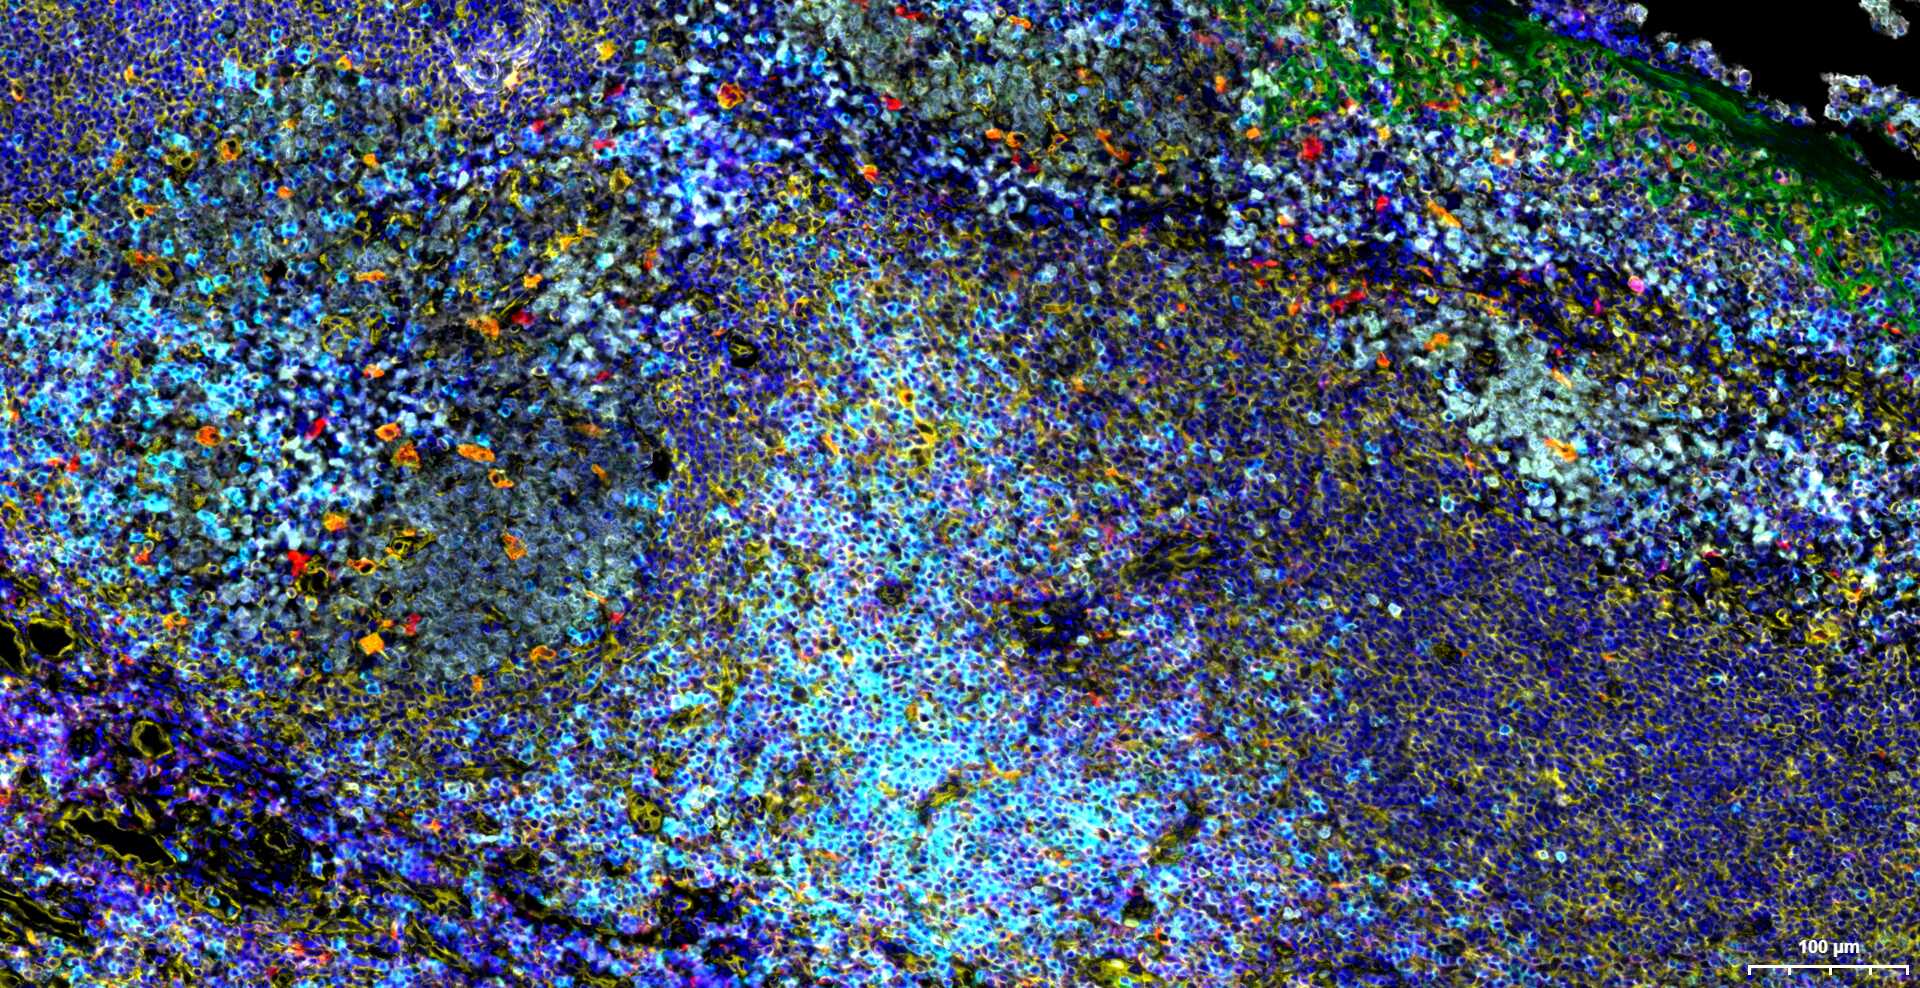

IHC-PHuman1:100-500

IHC-FHuman1:100-500

IFHuman1:100-500